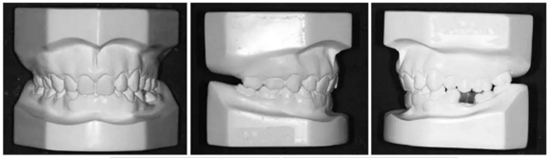

在治療結(jié)束時(shí),面部基本對(duì)稱(Figure 7)。上中線與面中線重合,下中線向左偏0.5mm,傾斜的合平面得到矯正,獲得了良好的咬合關(guān)系,具有正常的覆合和覆蓋,留下7mm的空間用于植入左下前磨牙(Figure 8、9)。

10.jpg

11.jpg